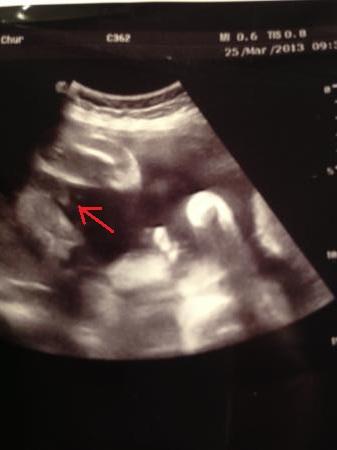

Hallo, es ist zunächst etwas schwierig, weil da ein großer Schallschatten drauf ist. Deswegen habe ich mir erlaubt, Dein Bild ein bisschen zu bearbeiten. Ich habe es von meinem PC gleich wieder gelöscht ;-) Und man sieht absolut, ganz klar und eindeutig: JUNGE! LG, Julia P.S. So ähnlich sah es bei meinen beiden Jungs auch aus.

Bild zu

Oben links sehe ich den Po links und rechts davon die Beinchen. Also das dazwischen ist ein kleiner pipimatz.

das bild ist nicht das allerbeste. hm. wenn das die beine sind, wo ich denke das sie es sind, dann würde ich auch junge sagen :o) aber ich finds nicht ganz eindeutig was da was ist auf dem bild :o) und ich persönlich würd dann wohl eher dem fachmann glauben als einer kollegin.